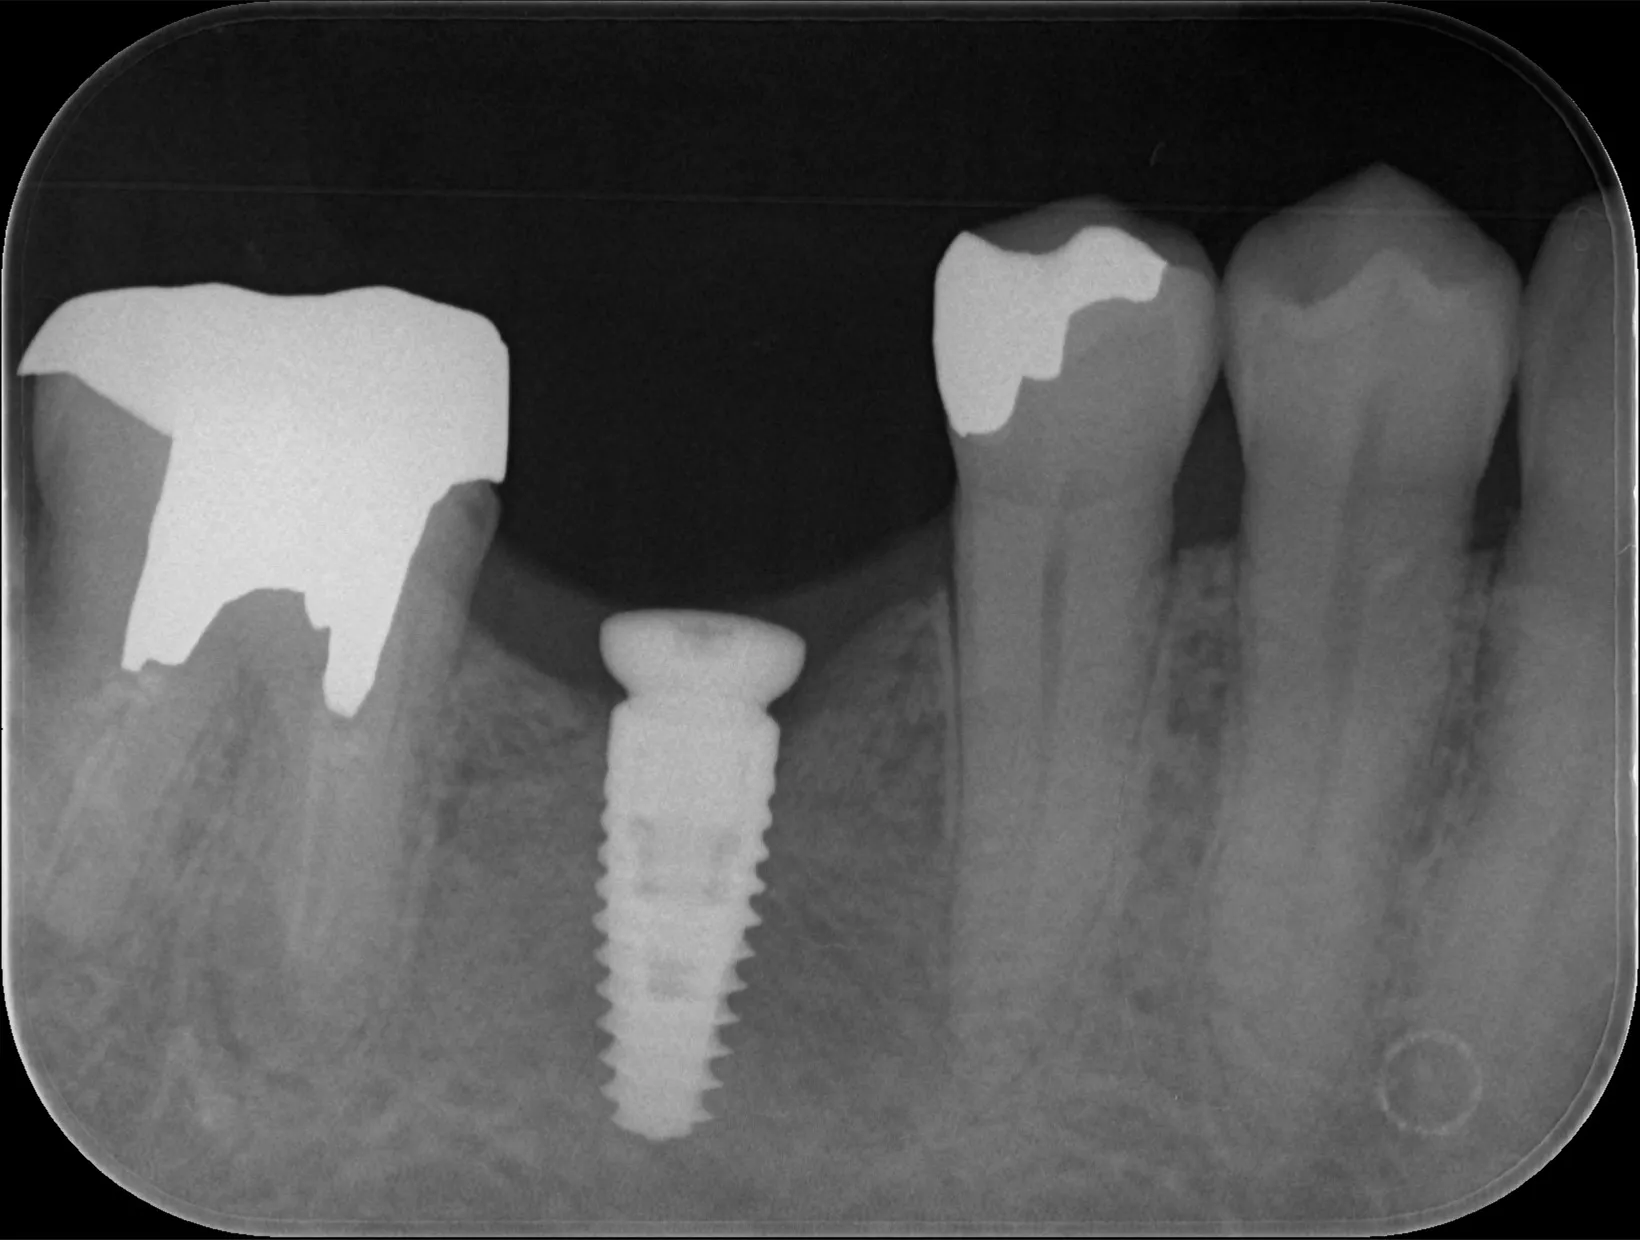

今回は抜歯になってしまった歯からインプラント治療完了までの流れについてご紹介いたします。